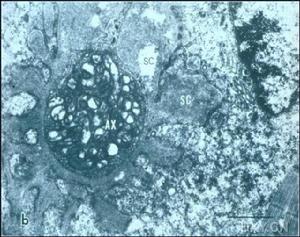

此2例患者均表現為四肢末端感覺障礙及下運動神經元癱瘓,結合肌電圖檢查,多發性神經病診斷可以成立。兩人同為海員,均長期在非洲毛利塔尼亞工作,同事中還有多人有類似症狀。患者飲食及飲水來自當地,存在維生素缺乏可能。輔助檢查發現葉酸明顯降低,予以補充葉酸後,症狀均逐漸緩解,故考慮為葉酸缺乏引起多發性神經病。葉酸參與體內DNA合成,並與維生素B12參與體內半胱氨酸代謝。其缺乏,可造成高半胱氨酸血症,增加腦血管病及胎兒神經管畸形危險性。其途徑為甲基四氫葉酸酯還原酶可催化5,10-甲基四氫葉酸酯,成為5-甲基四氫葉酸,而葉酸的激活使同型半胱氨酸甲基化,成為蛋氨酸[1]。而葉酸缺乏引起多發性神經病,可能為周圍神經脫髓鞘病變的機制,尚需進一步研究。